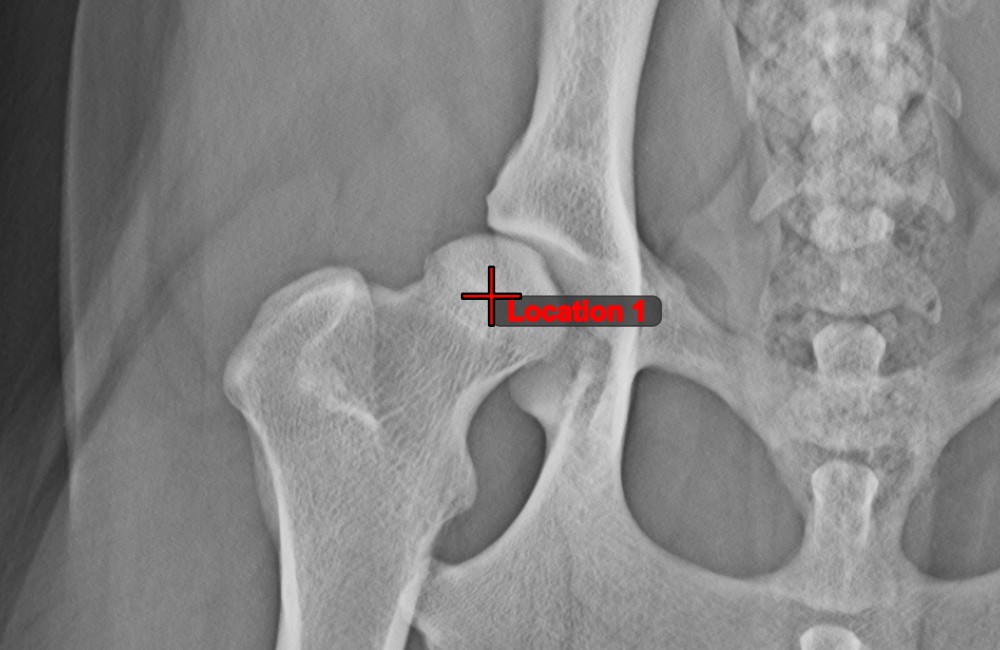

Pont létrehozása¶

Pont létrehozása eszközzel. Minden pont egy jelölő betűt kap a jobb azonosíthatóság érdekében.Elem kiválasztása/mozgatása eszközzel. Válassza ki a pontot az eszközhöz rendelt egérgomb segítségével, majd mozgassa szabadon a kép bármely részére.